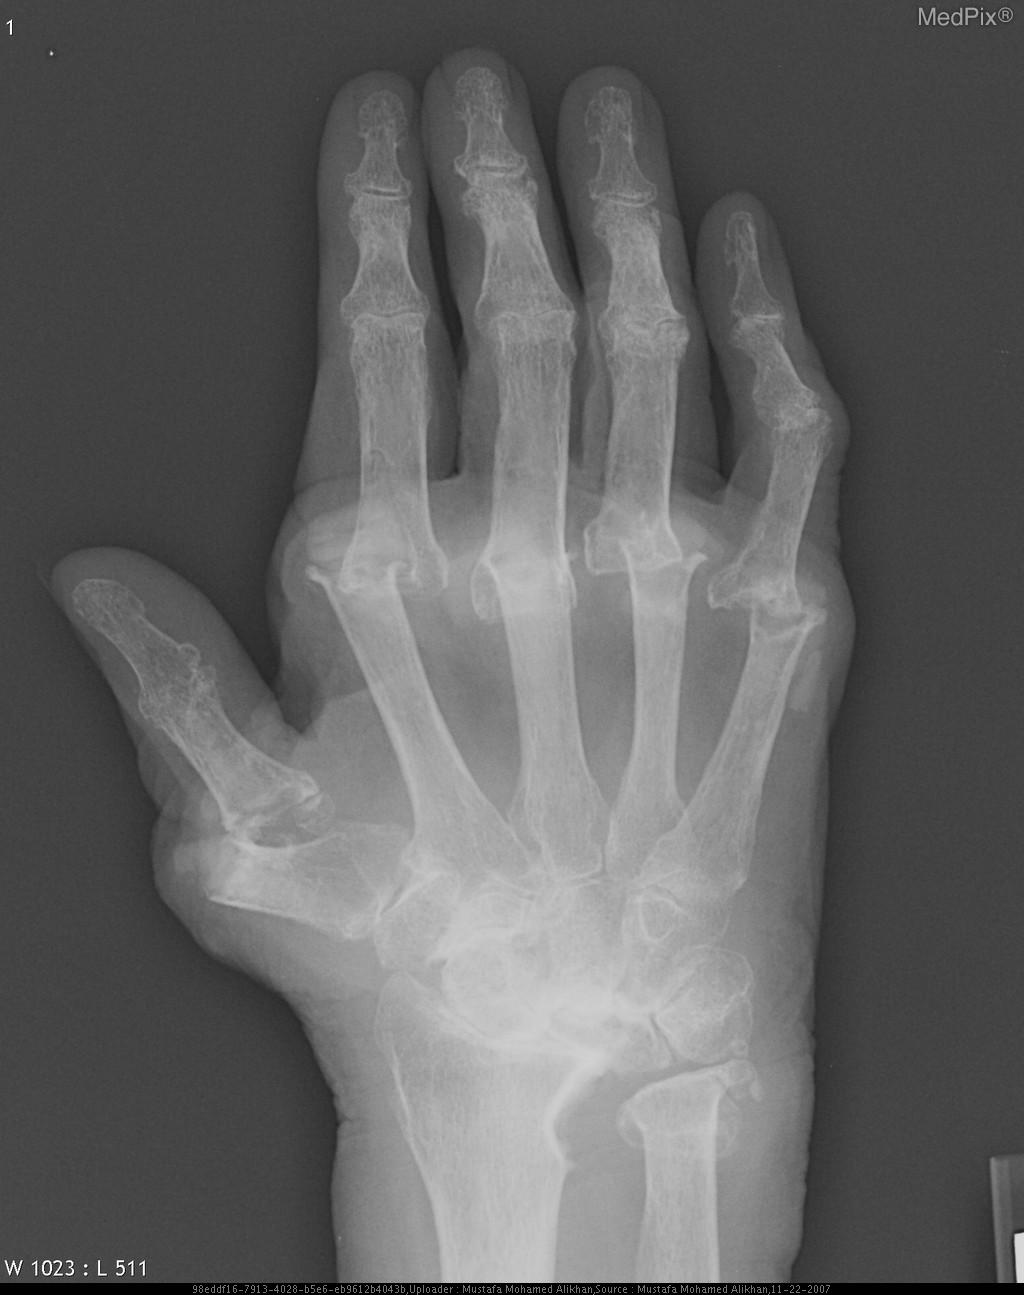

Arthritis is joint inflammation caused when the cartilage on joint surfaces gets worn down. It causes pain, swelling, noisy crackling or grating sounds in the joint with movement, stiffness, loss of motion and weakness at joints. Symptoms usually increase with prolonged positions, over use, or repetitive motions. The most common type is osteoarthritis (OA), which occurs as we age and is considered to be a degenerative joint disease. PT can help to support affected joints by strengthening surrounding muscles, maintaining range of motion, and relieving pain and muscle spasm. Regular safe exercise is very important for controlling OA. PT’s here at Goodell PT are trained to develop safe and effective exercise programs tailored specifically to the joints that are painful.